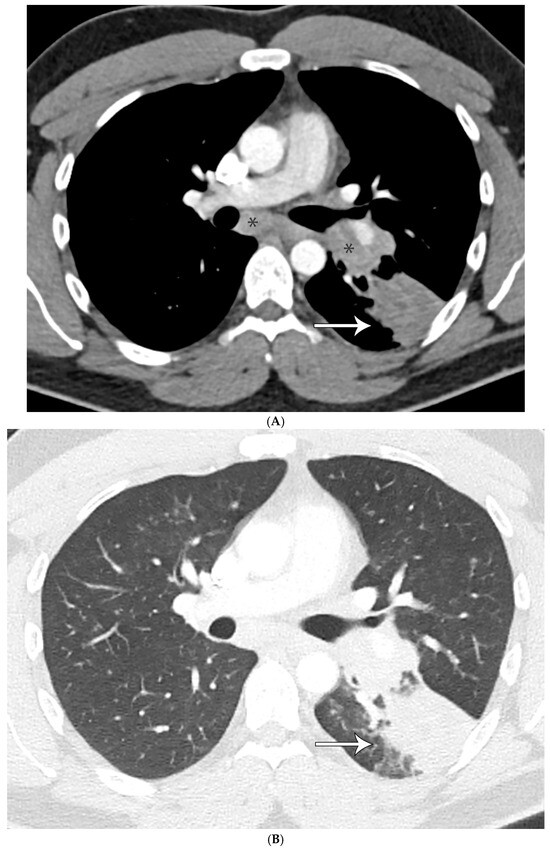

Cryptococcus spp.: Even though a granulomatous inflammation was present, lesions also showed more cellularity accompanied by inflammatory cells and multinucleated giant cells. Histochemical stains for GMS showed numerous organisms that also stained positively using mucicarmine stain (Figure 2A–C) and were morphologically compatible with cryptococcus spp.

Figure 2.

(A) Granulomatous inflammation replacing lung parenchyma with numerous giant cells; (B) GMS shows numerous fungal organisms; and (C) Cryptococcus spp. showing positive staining of the capsule with mucicarmine histochemical stain.